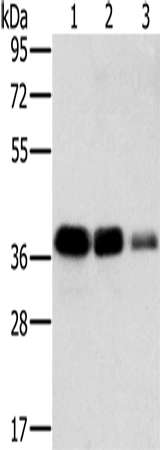

分类: 科研抗体货号: P01508别名: GBP; ECHA; HADH; LCEH; MTPA; LCHAD; TP-ALPHA应用: WB,IHC反应种属: Human, Mouse, Rat